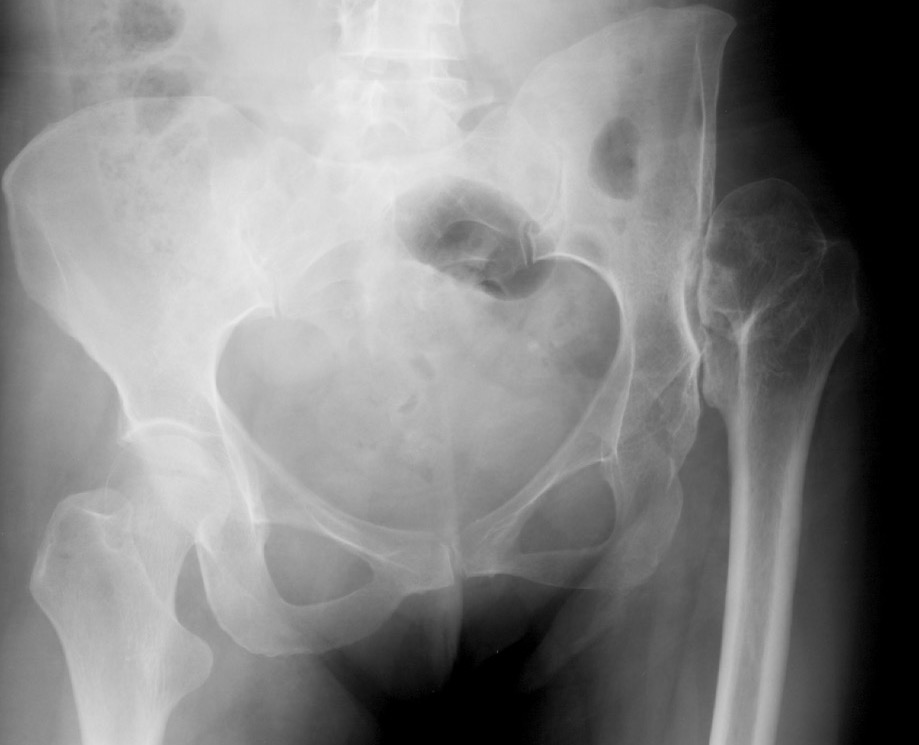

Crowe I

Crowe II

Crowe III

Crowe IV